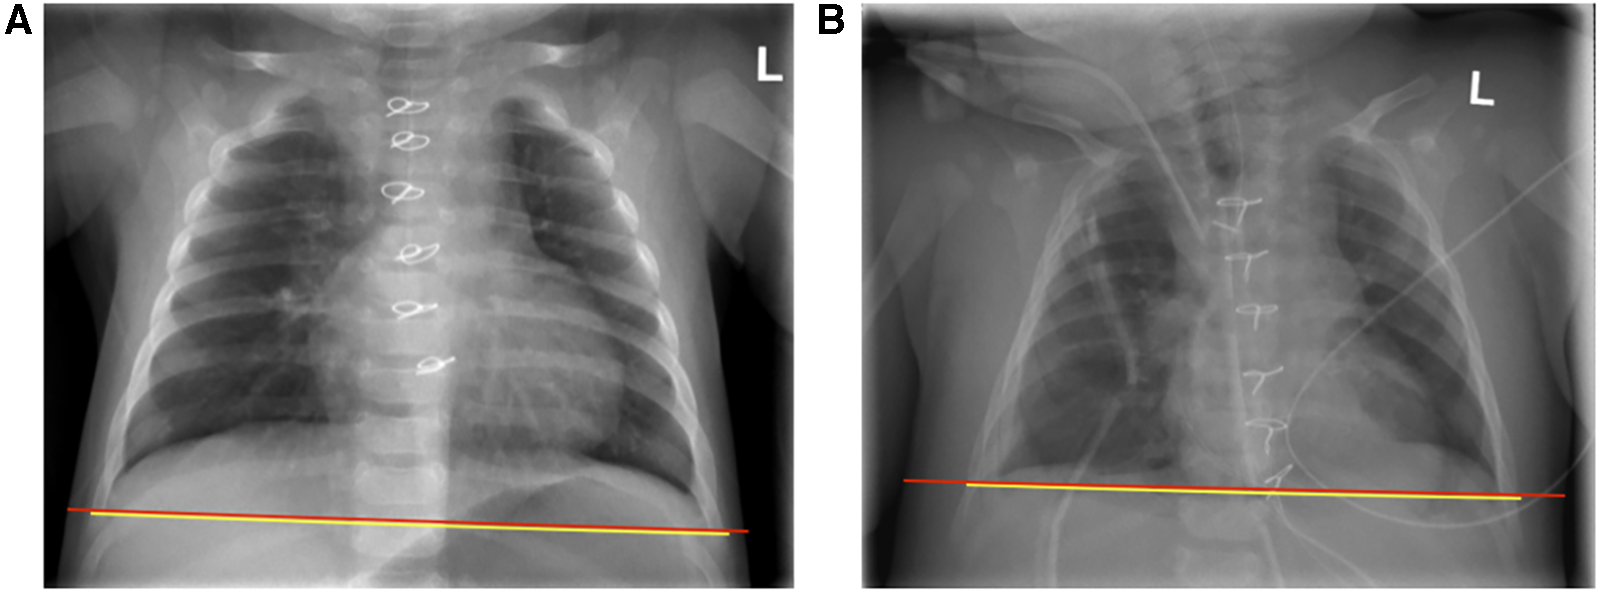

Duration of mechanical ventilation and maximum as well as mean vasoactive-inotropic score (VIS) was comparable in both male and female patients. However, duration of stay on the PICU was longer in male compared to female patients (median 31 h and 9 h, respectively as summarized in Table 3). Acute kidney injury as defined by KDIGO criteria, infections, and arrhythmia presented frequent complications in our patient cohort (Table 3) (51). One patient showed respiratory failure, hemodynamic instability, and increased demand for volume and catecholamines after modified Fontan procedure and was re-intubated during the first 24 h after initial surgery (55, 56). After catheterization on the first postoperative day, the patient received a re-thoracotomy and takedown of the Fontan-procedure. Another patient showed an atrioventricular block III° postoperatively and received a transvenous pacemaker 10 days after initial cardiac surgery. S/T-ratio and fluid overload were assessed as criteria for CLS. In 7 patients S/T ratio was not analyzable due to a cut off soft tissue on the x-ray. 3 patients showed an S/T-ratio >12.6% during the first 72 h after CPB (an exemplary chest x-ray analysis is shown in Figure 2). During the first 24 h after operation both male and female patients presented a median fluid overload of 16% (Table 3). None of the enrolled patients died during hospitalization, 30-day mortality was 0% in both male and female patients. One patient with univentricular heart physiology was released after initial shunt operation and 6 weeks later readmitted to another hospital due to gastroenteritis. Two days after readmission the patient had an in-hospital cardiac arrest most likely due to shunt thrombosis, was transferred to our hospital under resuscitation conditions, where we ended the treatment due to the poor prognosis.

Figure 2

Example of chest x-ray analysis for assessment of subcutaneous-thoracic (S/T) ratio according to sonntag et al. (52) (A) Pre- and (B) postoperative x-rays of a patient with an S/T-ratio 16.8.